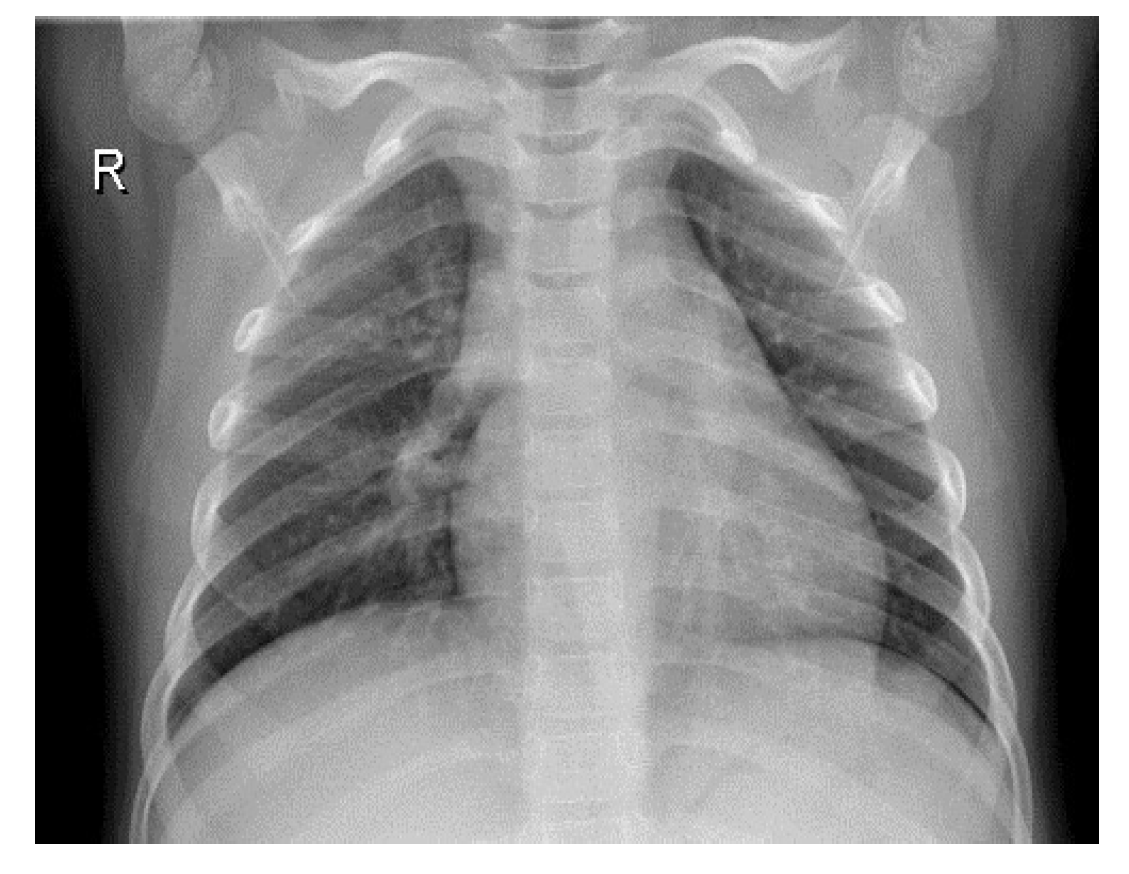

To improve the authenticity of the research, this paper selected a large number of athletes from professional sports colleges. X-ray images of the above athletes’ lungs were collected. There were 2806 men and 2806 women, totaling 5612, accounting for 30% of the unit athletes in 2020. The ages were between 18 and 25 years old. The shortest training period was only 1 year and the longest training period was 5 years. Figure 6 and Figure 7 are the medical images of the part collected.

Figure 7. Lung image with pneumonia.

Entropy 24 01434 g007